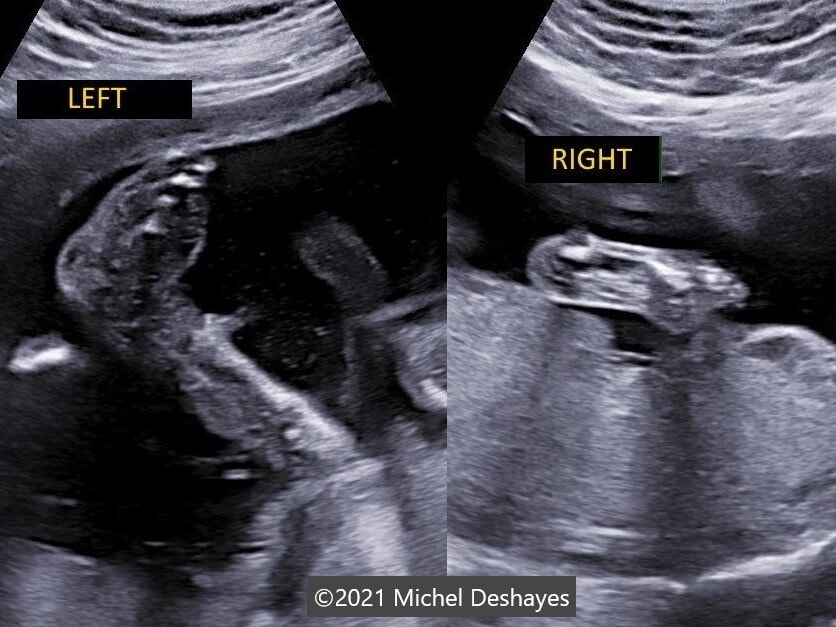

• Images 8,9: Ultrasound at 23 weeks gestation showing an amniotic band near the external right ear causing a stricture on 3D image.